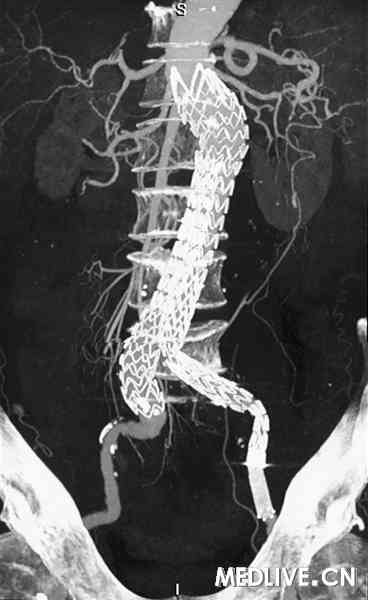

56岁男性患者,因“发现左下腹搏动性包块1个月,反复疼痛1周”入院。既往患者有高血压病3年;入院时血压为180/90 mmHg,左下腹有一个3 cm×3 cm搏动性包块。CT血管造影(CTA)示腹主、左髂总动脉瘤形成,瘤体最大直径分别为4.6 cm和3.7 cm(图1)。患者接受覆膜支架腔内修复术后(图2)痊愈出院。

图2 覆膜支架腔内修复术后 |